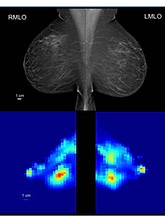

Healthy participant and tumor detection figures adapted from Mojabi P, Tsang RY, Docktor B, et al. Feasibility of tumor detection with a transmission-based microwave imaging system. Med Phys. 2025; 52:e18080. https://doi.org/10.1002/mp.18080 © 2025 The Author(s). https://creativecommons.org/licenses/by/4.0/. Figures displayed in orientation familiar to radiologists.

Breast composition figure © 2025 IEEE. All rights reserved, including rights for text and data mining and training of artificial intelligence and similar technologies. Reprinted with permission from Mojabi et al, Assessment of Breast Composition with A Transmission-based Microwave Imaging System. IEEE Transactions on Biomedical Engineering, 2025.